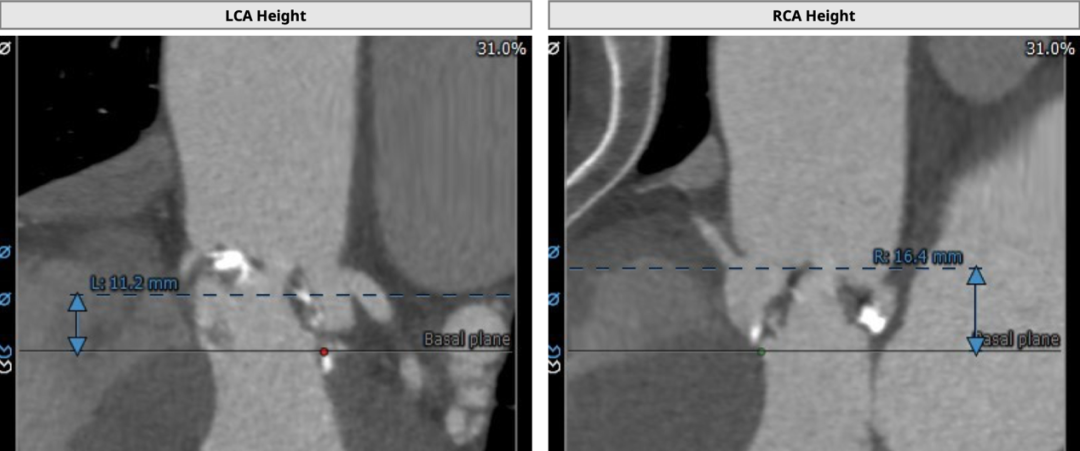

为三叶式主动脉瓣,瓣叶钙化较重,瓣环周长获得平均直径23.5mm,左右冠脉开口高度分别为11.2和16.4mm。瓣叶冗长,左冠开口水平可见瓣叶,左冠有堵塞风险。双侧股动脉走行流畅,无明显钙化迂曲,左右最细处分别为6.5和6.6mm。